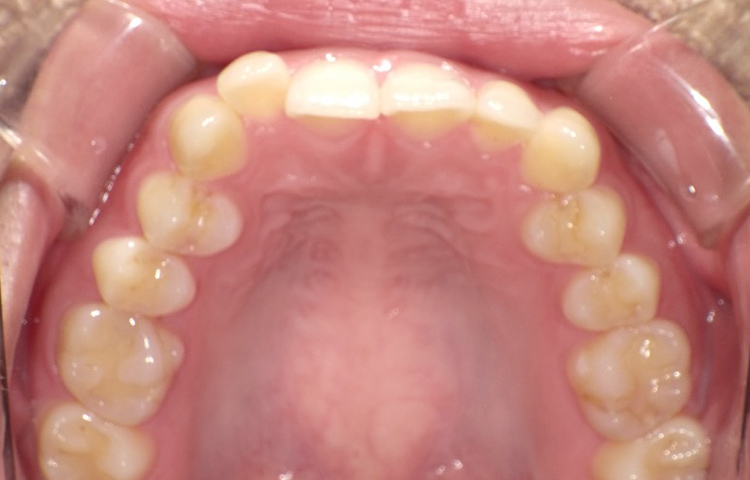

治療前

治療後

| 主訴 | 上の前歯のガタつきが気になるので前歯だけ綺麗にして欲しい |

|---|---|

| 治療 期間 |

約6ヶ月 |

| 治療費 | 165,000円(税込)/調整費用別途 |

| 治療 内容 |

上の前歯部にワイヤーを着けて進めていく、プチ矯正で施術。 |

| 治療の リスク |

見た目を綺麗にする目的で短期間で仕上げる為噛み合わせは矯正しない。 |